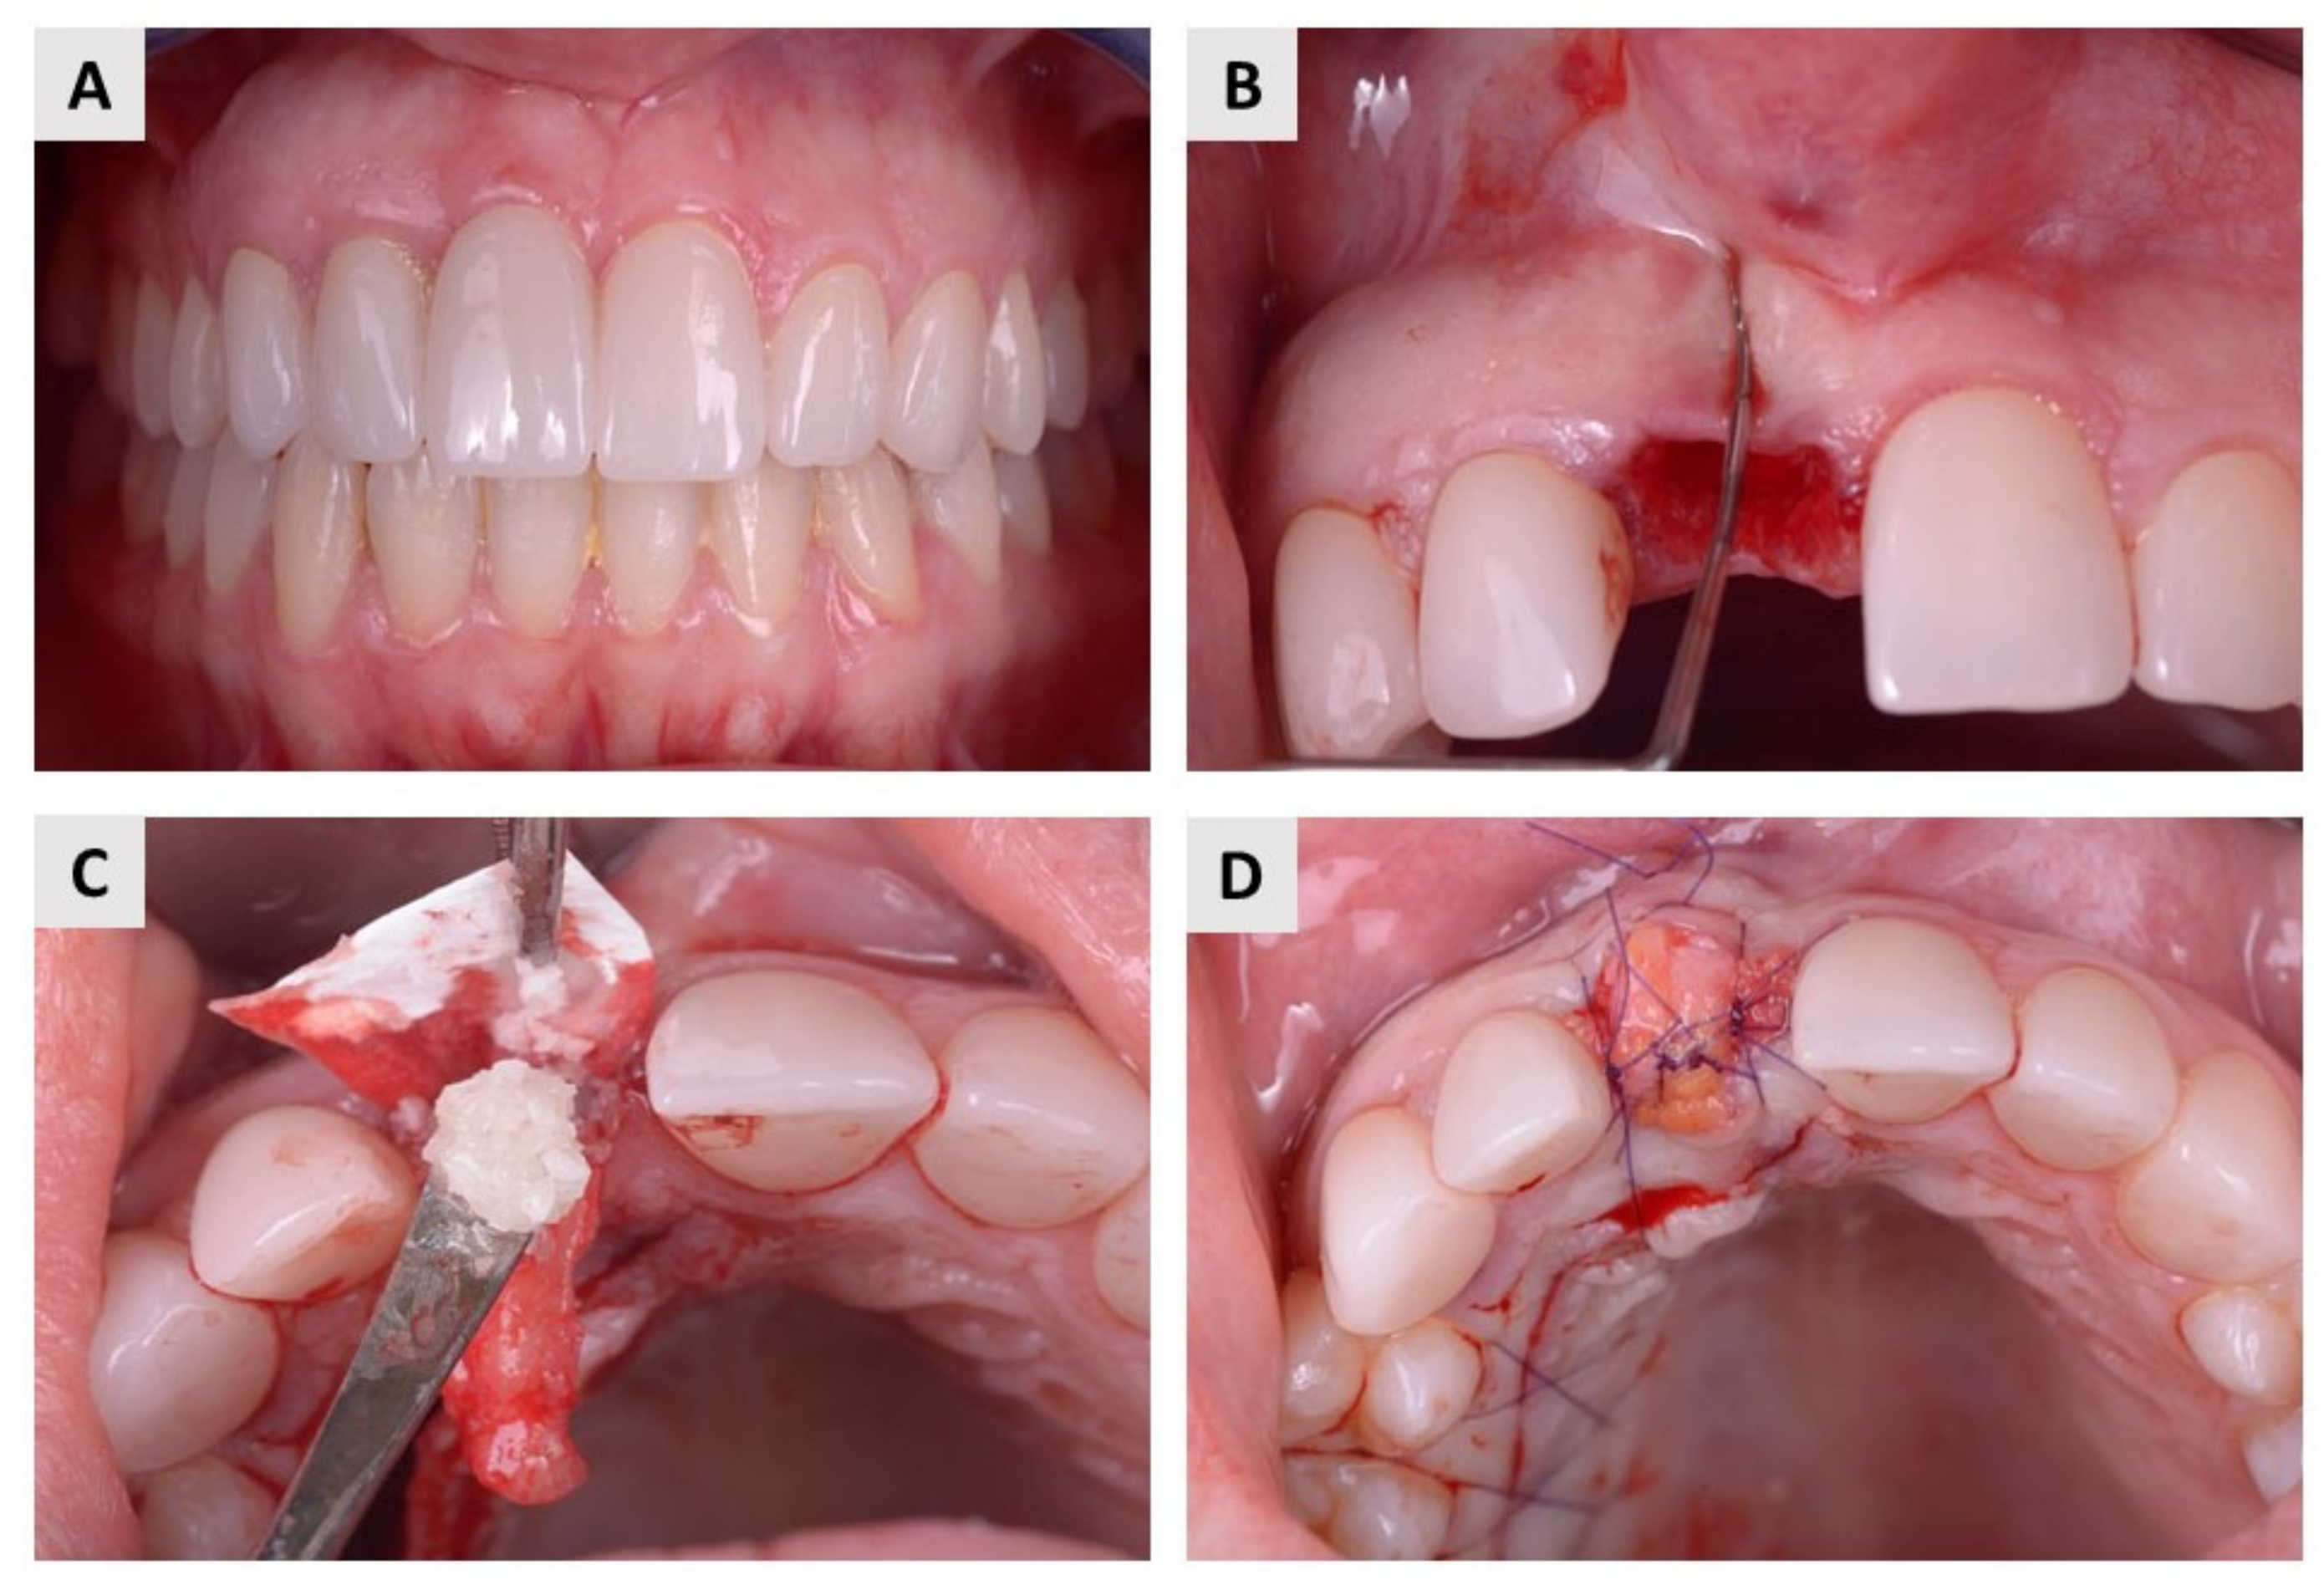

4.2. Surgical Procedure and Postoperative Follow-Up